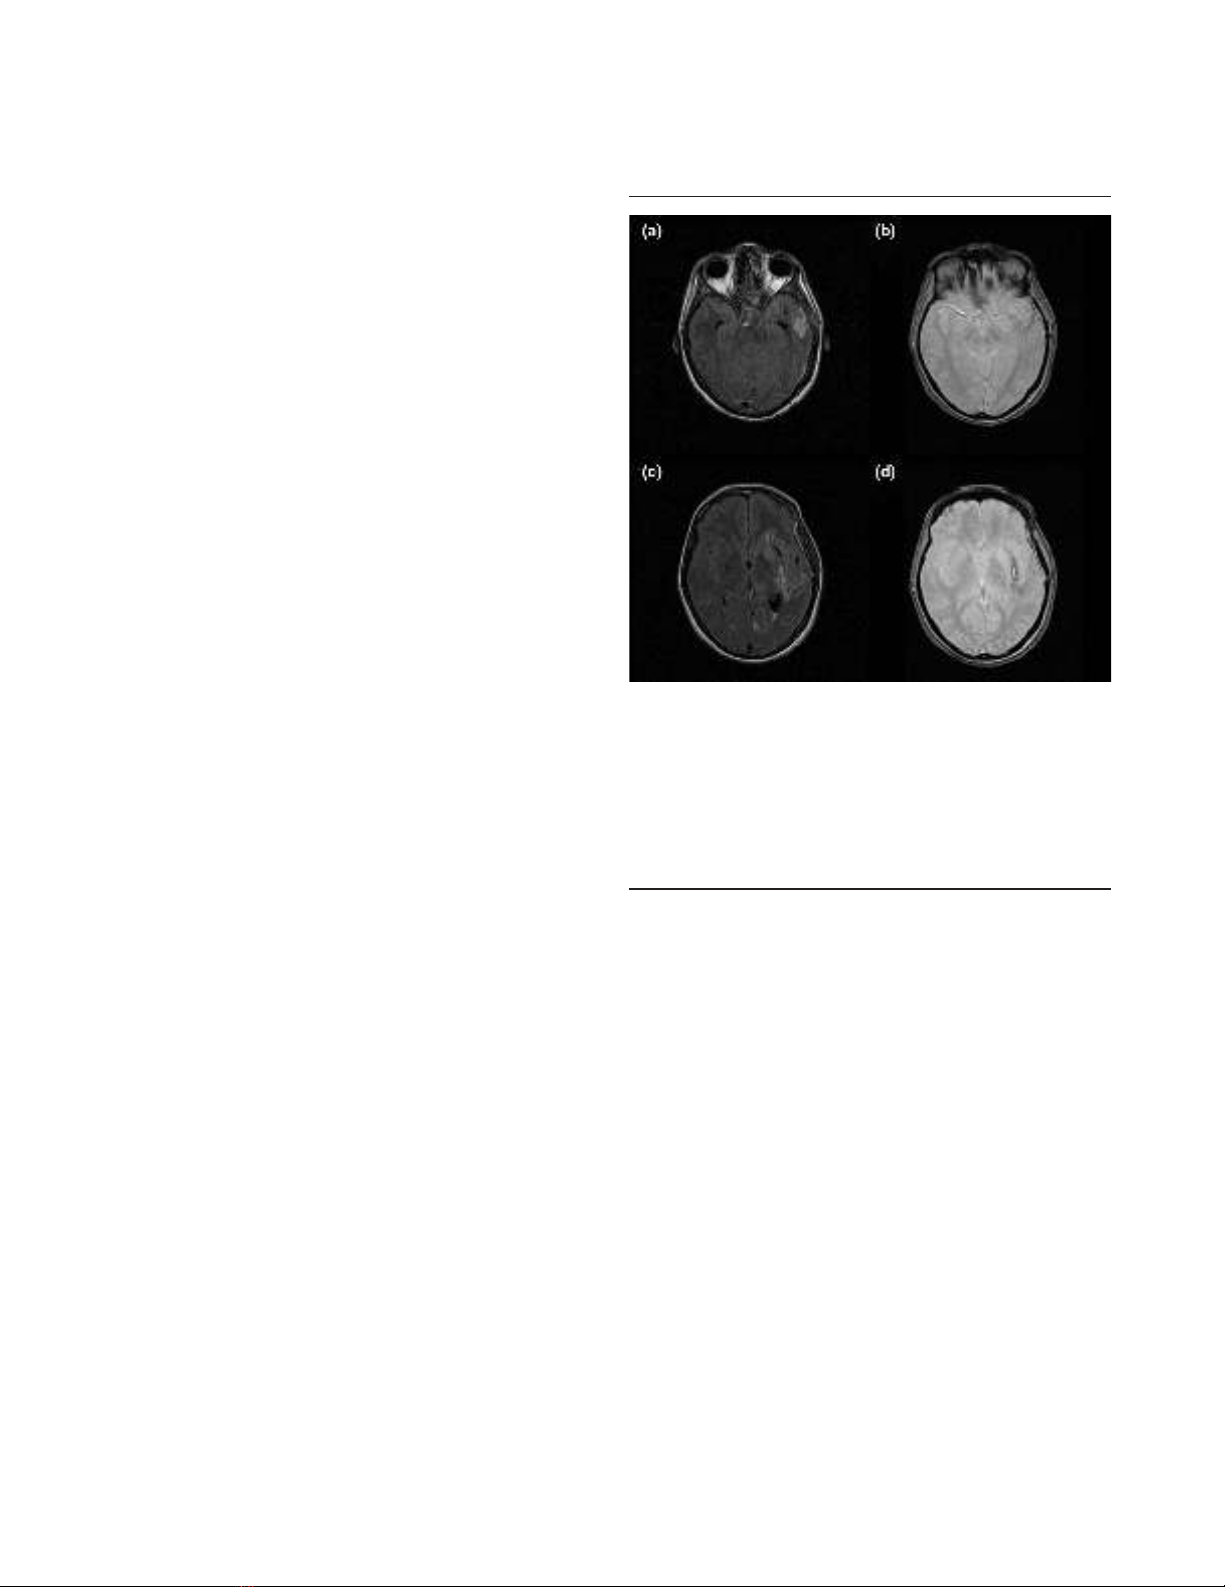

Figure 1

FLAIR and T2* sequences in a patient with an arteriovenous

malformation. (a) Axial fluid-attenuated inversion recovery (FLAIR)

sequence showing hypersignal in the left temporal lobe. (b) Axial T2*

sequence showing mild hyposignal in the same area suggestive of

bleeding. (c) Different section of the axial FLAIR sequence showing

hypersignal surrounded by hyposignal. Bleeding cannot be confirmed.

(d) Axial T2* sequence clearly showing hyposignal lateral to the left

putamen. The patient has bleeding from the arteriovenous

malformation.

Conventional MRI relies chiefly on four sequences [6]. Fluid-

attenuated inversion recovery (FLAIR) is the primary

sequence used in neuroradiology (Figure 1). It detects brain

contusion, brain oedema and subarachnoid or intraventricular

haemorrhage, as well as the resulting ventricular dilatation or

herniation. The T2*-weighted sequence is more sensitive to

intraparenchymal blood than is FLAIR. This sequence can

also reveal haemorrhagic DAI [7,8]. The T2-weighted

sequence completes the FLAIR sequence and provides

greater detail on brainstem and central grey matter. Finally,